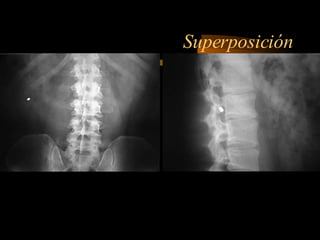

La tomografía computada fue desarrollada por Sir Godfrey Hounsfield y Allan Cormack, quienes recibieron el Premio Nobel de Fisiología o Medicina en 1979 por su trabajo pionero en la aplicación de la computación para generar imágenes transversales del cuerpo humano. La tomografía computada utiliza rayos X y computadoras para crear imágenes transversales del cuerpo.